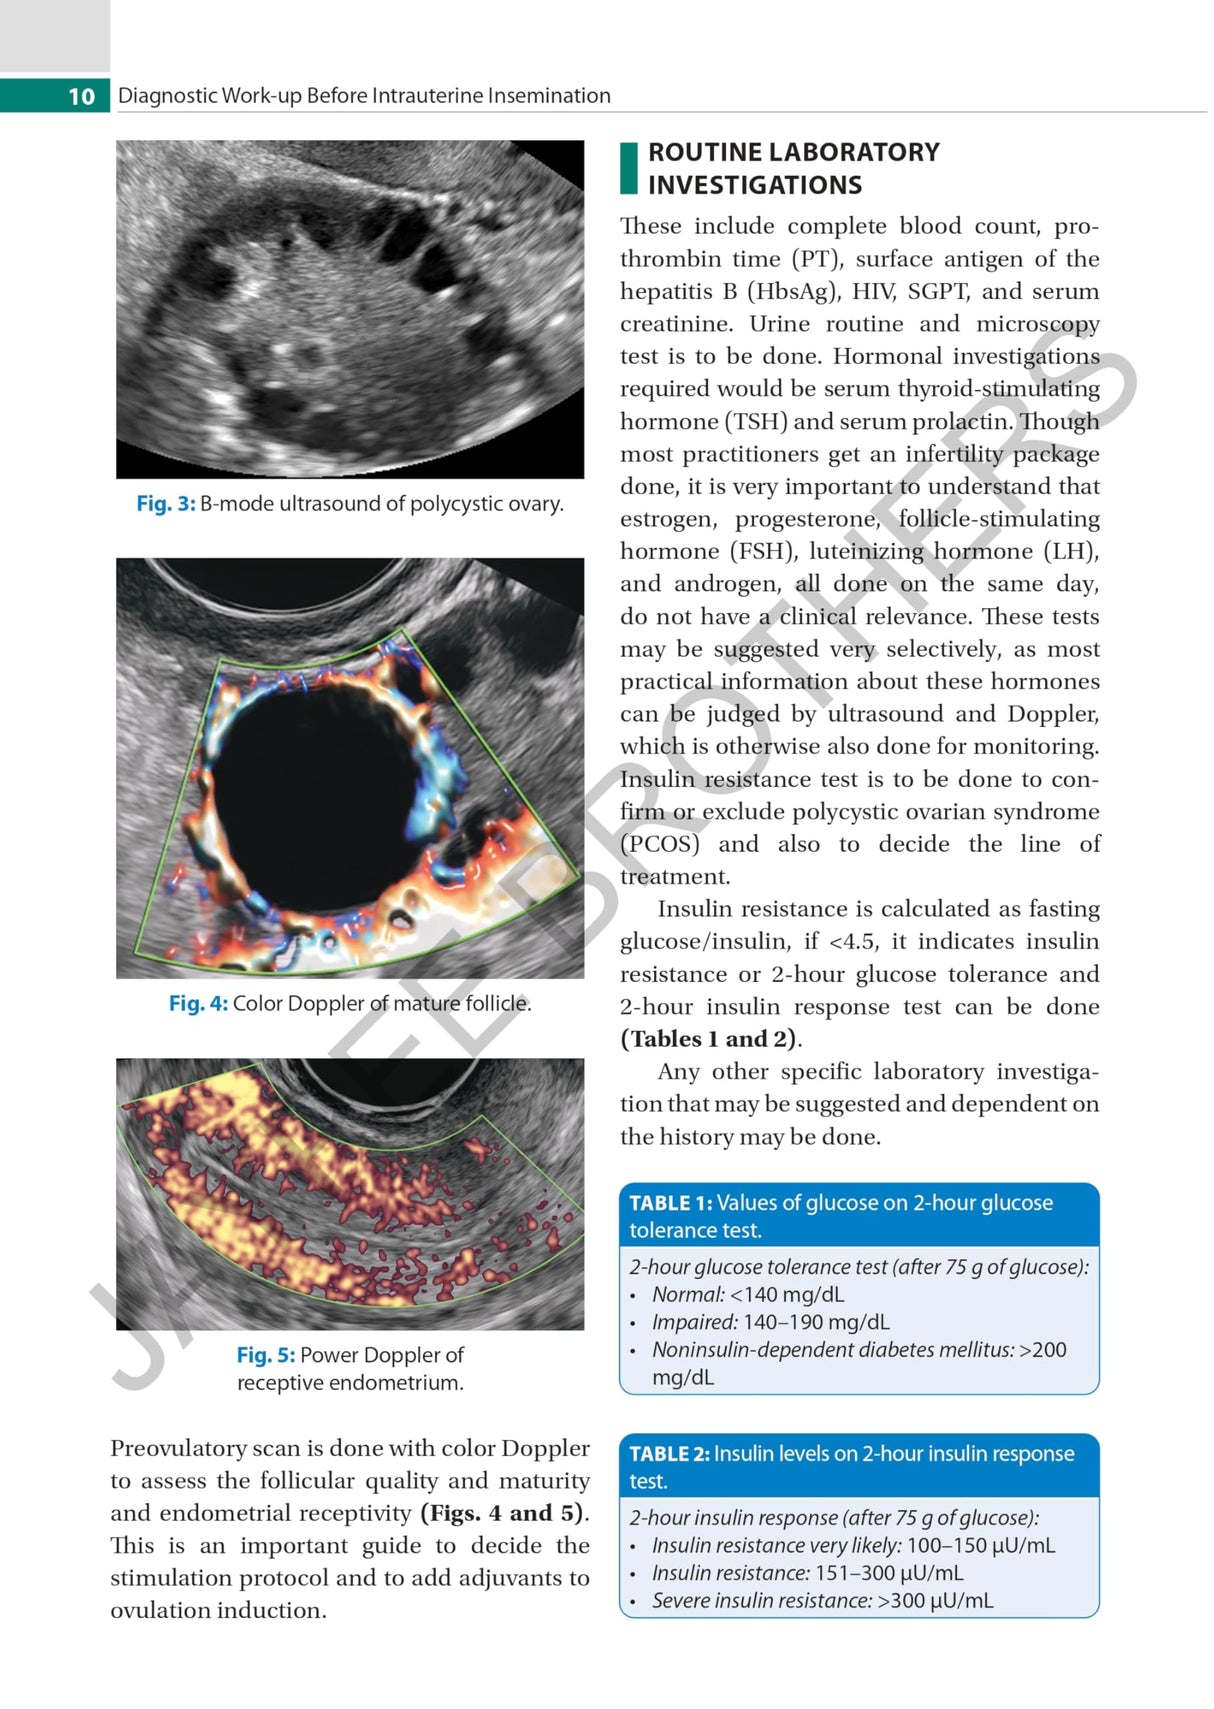

Beginning with discussion on counselling and diagnostic work-up before IUI, the next chapters cover indications and ultrasound. The following sections examine ovulation, timing of IUI, techniques, luteal phase support, complications, and factors affecting success. The final chapter discusses sperm preparation.

The text is further enhanced by clinical images and figures.